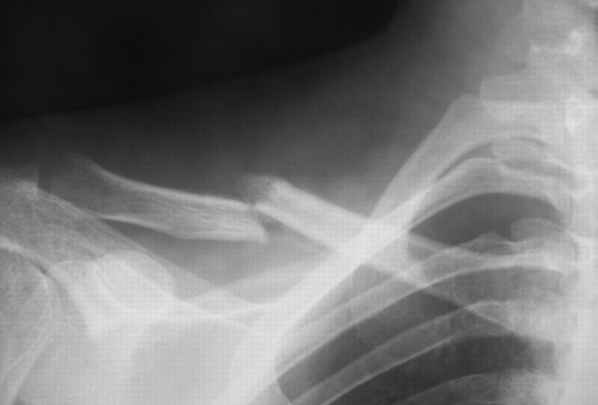

В приложении проект наших тезисов на съезд и клинический пример: Пациентка 23 лет поле неэффективного оперативного лечения (4 нед.) перелома ключицы спицей (была оперирована в С-Петербурге)(снимок после удаления спицы) и результат закрытого БИОС..